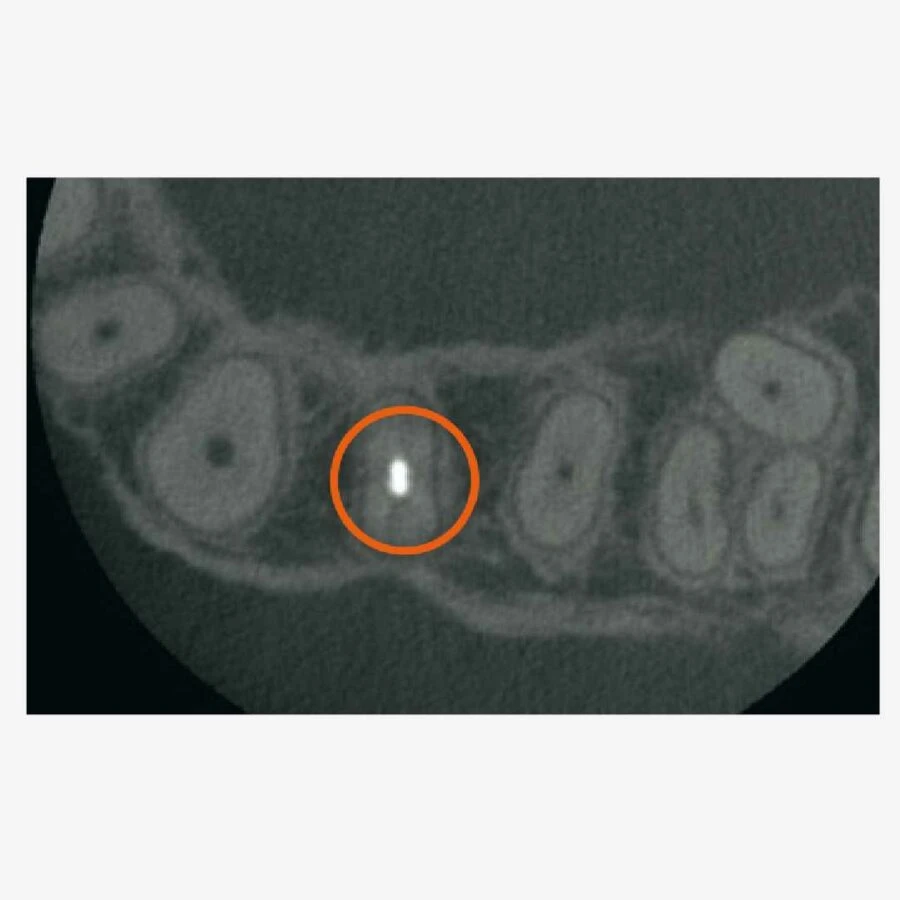

Trường nhìn máy x-quang nha khoa 3D toàn hàm dạng tam giác

Khu vực tiếp xúc dành cho nhiều Dianostics

– Với 6 lựa chọn trường nhìn và chất lượng hình ảnh nổi tiếng thế giới của Morita, X550 phù hợp cho các ứng dụng đa dạng trong nha khoa bao gồm phương án cấy ghép.

– Khả năng chụp toàn bộ vòm miệng, giảm liều tia và rất rõ ràng là các đặc điểm lý tưởng cho việc lên kế hoạch cấy ghép và phẫu thuật miệng.